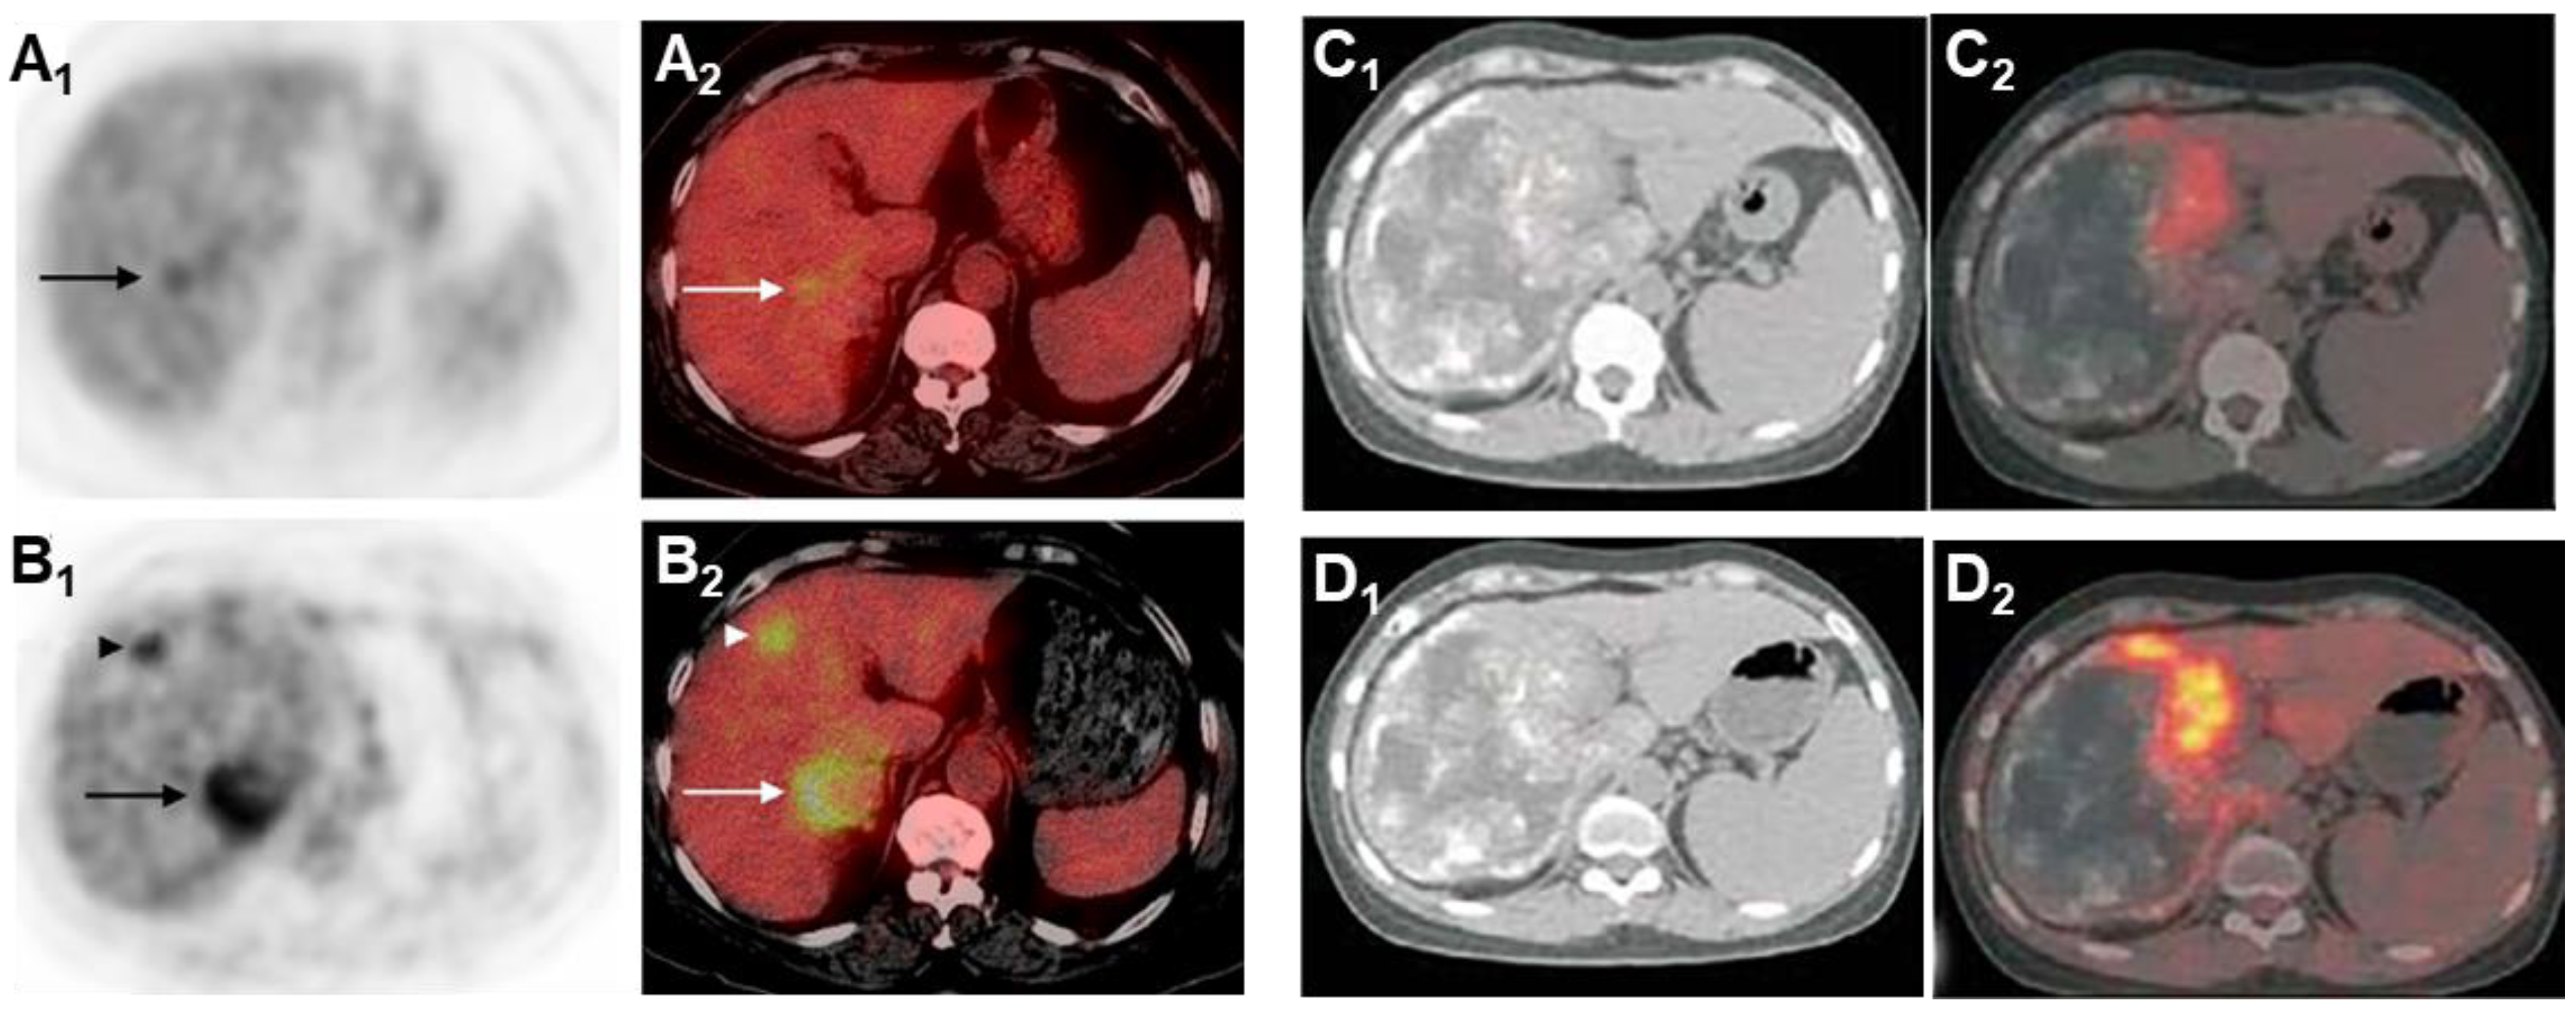

FDG-PET is also used for long-term follow-up of AE (Figure 10). The absence of metabolic activity indicates suppression of parasite activity, which is not equivalent to parasite death. This suppression can persist for several years, and oral medication therapy should be reinitiated when recurrence is detected by PET [167,168,169]. In a retrospective study of 179 AE patients who underwent PET/CT scans, it was found that as the clinical status progressed, significant changes occurred in total immunoglobulin E (IgE), parasite-specific IgE, and serological status (using crude antigen preparations or recombinant/purified antigens such as EM10, Em18, and Em2) [170]. Notably, these serological biomarkers were also significantly higher in patients with positive PET results. Multiple studies have shown that combining FDG-PET with serological testing can further improve the accuracy of parasite activity identification [171]. For patients with AE who are unable to undergo surgical resection, oral albendazole treatment is often prescribed; the treatment usually is life-long. For patients with inactive disease, a structured treatment interruption (STI) of drug therapy may be a goal, not only to save costs but also to improve quality of life. Ammann et al. [172] evaluated FDG-PET/CT and antibody levels against recombinant Emll/3-10 antigen as markers of parasite vitality, serving as a reliable tool to allow for the selection of patients who can safely discontinue chemotherapy with a low risk of AE recurrence. Husmann et al. [173] hold the view that negative FDG-PET/CT results combined with no detectable levels of Em-18 antibodies may allow for the safe discontinuation of benzimidazole therapy in patients with AE. The quantitative imaging parameter SUVratio, obtained through PET/CT, correlates with the time to reach no detectable levels of Em-18 antibodies and the duration of benzimidazole treatment. In patients presenting negative results for both indicators, a watch-and-wait strategy might be permissible [174].